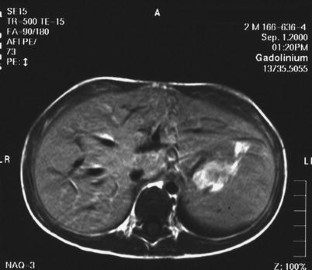

Fig. 1